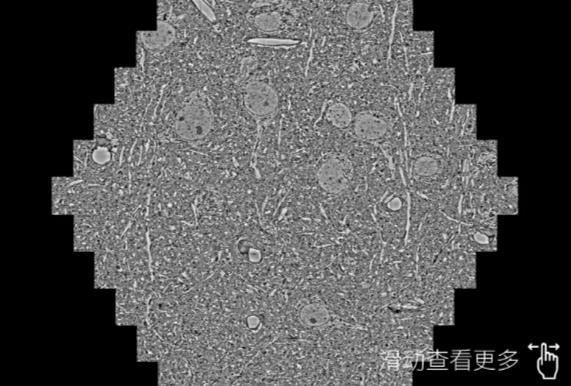

鼠脑切片。左图使用菏泽蔡司菏泽扫描电镜MultiSEM706对165μmx143pm面积区域成像,耗时仅需1.5秒。右图为鼠脑切片中30μm区域放大效果。样品由芝加哥大学B.Kasthuri提供。

使用蔡司高速菏泽扫描电镜MultiSEM对1mm²人脑皮层组织进行高分辨成像,并对其中的各种细胞结构进行三维重构分析。左图展示了2x3mm²组织平面中锥体神经元的三维重构效果。右图显示了局部体积神经元三维重构。图像由哈佛大学chtman实验室提供,渲染图由D. Berger 制作。